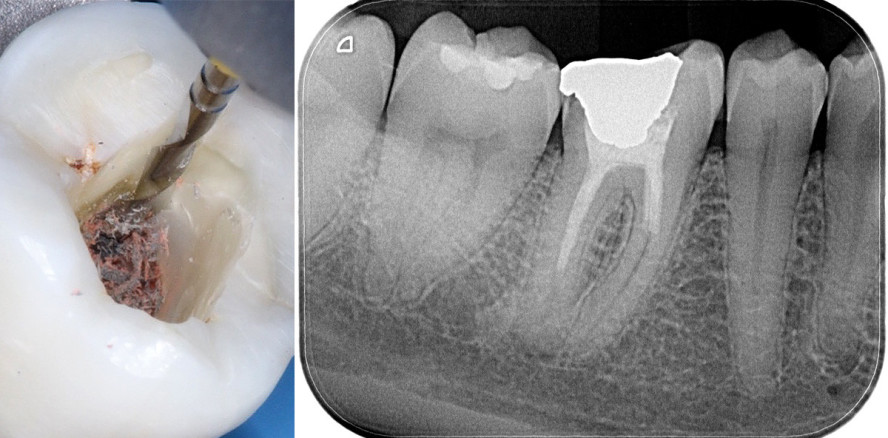

Wenn eine endodontische Behandlung fehlschlägt, kann dies durch den Verbleib von Bakterien im Innern des Wurzelkanalsystems bedingt sein. Es kann die Folge einer unzureichenden Desinfektion, einer ungeeigneten Obturation oder einer schwindenden, koronalen Versiegelung sein.1 Der Fehler kann dann dank einer orthograden Revision2 oder durch einen chirurgischen Eingriff erfolgreich behoben werden. Die Technik ohne chirurgischen Eingriff erfordert die vollständige Entfernung des verbleibenden Wurzelfüllmaterials, welches sich in dem Wurzelkanalraum befindet, damit eine vollständige Desinfektion, gründlichere Formgebung und dreidimensionale Obturation des Wurzelkanalsystems erreicht werden kann. All dies sind unverzichtbare Bedingungen, um den Erfolg der Behandlung zu sichern (Abb. 1a–c).3 Für die Entfernung des Wurzelfüllmaterials werden verschiedene Techniken empfohlen, z. B. die Verwendung von rotierenden Nickel-Titan-Instrumenten4–7, von Ultraschallspitzen8–10, Hitzeträgern11,12 oder auch von Handinstrumenten in Kombination mit chemischen Lösungsmitteln, wie z. B. Eukalyptusöl13–15. Rotierende Nickel-Titan-Instrumente haben sich als bestens geeignet erwiesen, da sie die schnellste Entfernung des Wurzelfüllmaterials ermöglichen.16 Keine der vorgeschlagenen Techniken ist jedoch in der Lage, eine komplette Entfernung von Rückständen aus dem Wurzelkanal zu garantieren. Fest steht, dass eine Kombination verschiedener Methoden eine potenziell bessere Entfernung von Guttapercha und Zement aus dem Wurzelkanal sicherstellen kann.17

Nachdem eine sorgfältige Öffnung der Zugangskavität geschaffen und der Eingang des Wurzelkanals freigelegt wurde, wird zunächst der Opener eingesetzt. Dank seiner speziellen Spitze und hoher Stabilität ist dieses Instrument in der Lage, auch in sehr harte und stark komprimierte Materialien einzudringen, wie man sie häufig am Eingang des zu behandelnden Wurzelkanals vorfindet. Der Opener sollte nur im ersten koronalen Drittel des Kanals arbeiten. Er wird also vorbereitend eingesetzt und schafft eine Art „Einladung“ für das nachfolgende Instrument, die Feile. Je nach Länge des Kanals entscheidet sich der Zahnarzt für das Instrument in 21 mm (bei kürzeren Kanälen) oder 25 mm Länge (bei längeren Kanälen; Abb. 6). Aufgrund ihres Querschnitts und des Tapers .05 sind die Instrumente sehr flexibel und daher auch für den Gebrauch von gekrümmten Kanälen geeignet. Nachdem das Füllungsmaterial aus dem Wurzelkanal entfernt wurde, kann wie bei einer normalen endodontischen Behandlung mit der Festlegung der Arbeitslänge und der Bearbeitung des Wurzelkanals gemäß der vom Zahnarzt bevorzugten Aufbereitungstechnik fortgefahren werden.